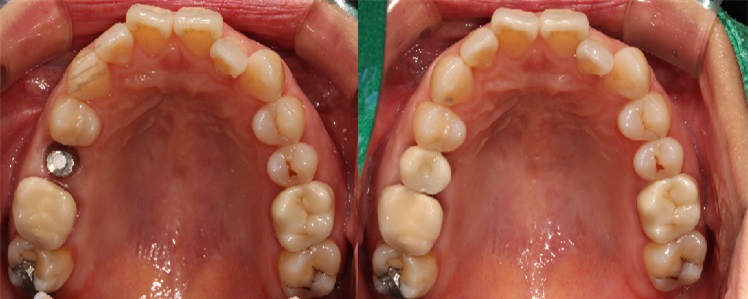

치료전후사진